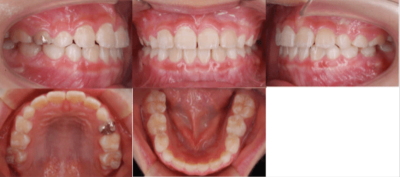

<治療前>

<治療後>

初診時は7歳2ヶ月で、前歯のかみ合わせが反対になっていることが主訴で来院されました。前歯部の反対咬合の診断により、「マウスピース型カスタムメイド矯正歯科装置(製品名インビザライン・ファースト 完成物薬機法対象外)」を使用して治療を開始しました。

治療期間は6ヶ月で、下顎の前歯が上顎の前歯より前に出ている「交叉咬合」が改善されました。

治療のリスクとしては、矯正治療時に歯が移動する際に生じる痛み、歯根の吸収、むし歯が挙げられます。治療費用はおよそ40万円です。